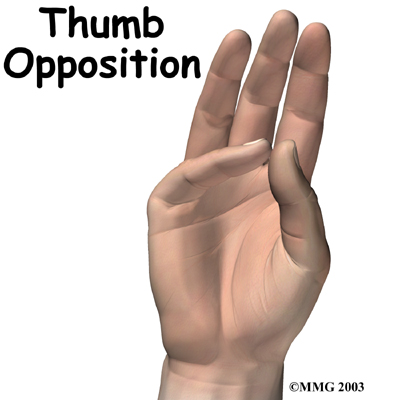

Most of the small muscles that work the thumb and pinky finger start on the carpal bones. connect in ways that allow the hand to grip and hold. Two muscles allow the thumb to move across the palm of the hand, an important function called .

The travels through a tunnel within the wrist called the carpal tunnel. This nerve gives sensation to the thumb, index finger, long finger, and half of the ring finger. It also sends a nerve branch to control the thenar muscles of the thumb. The thenar muscles help move the thumb and let you touch the pad of the thumb to the tips each of each finger on the same hand, a motion called opposition.